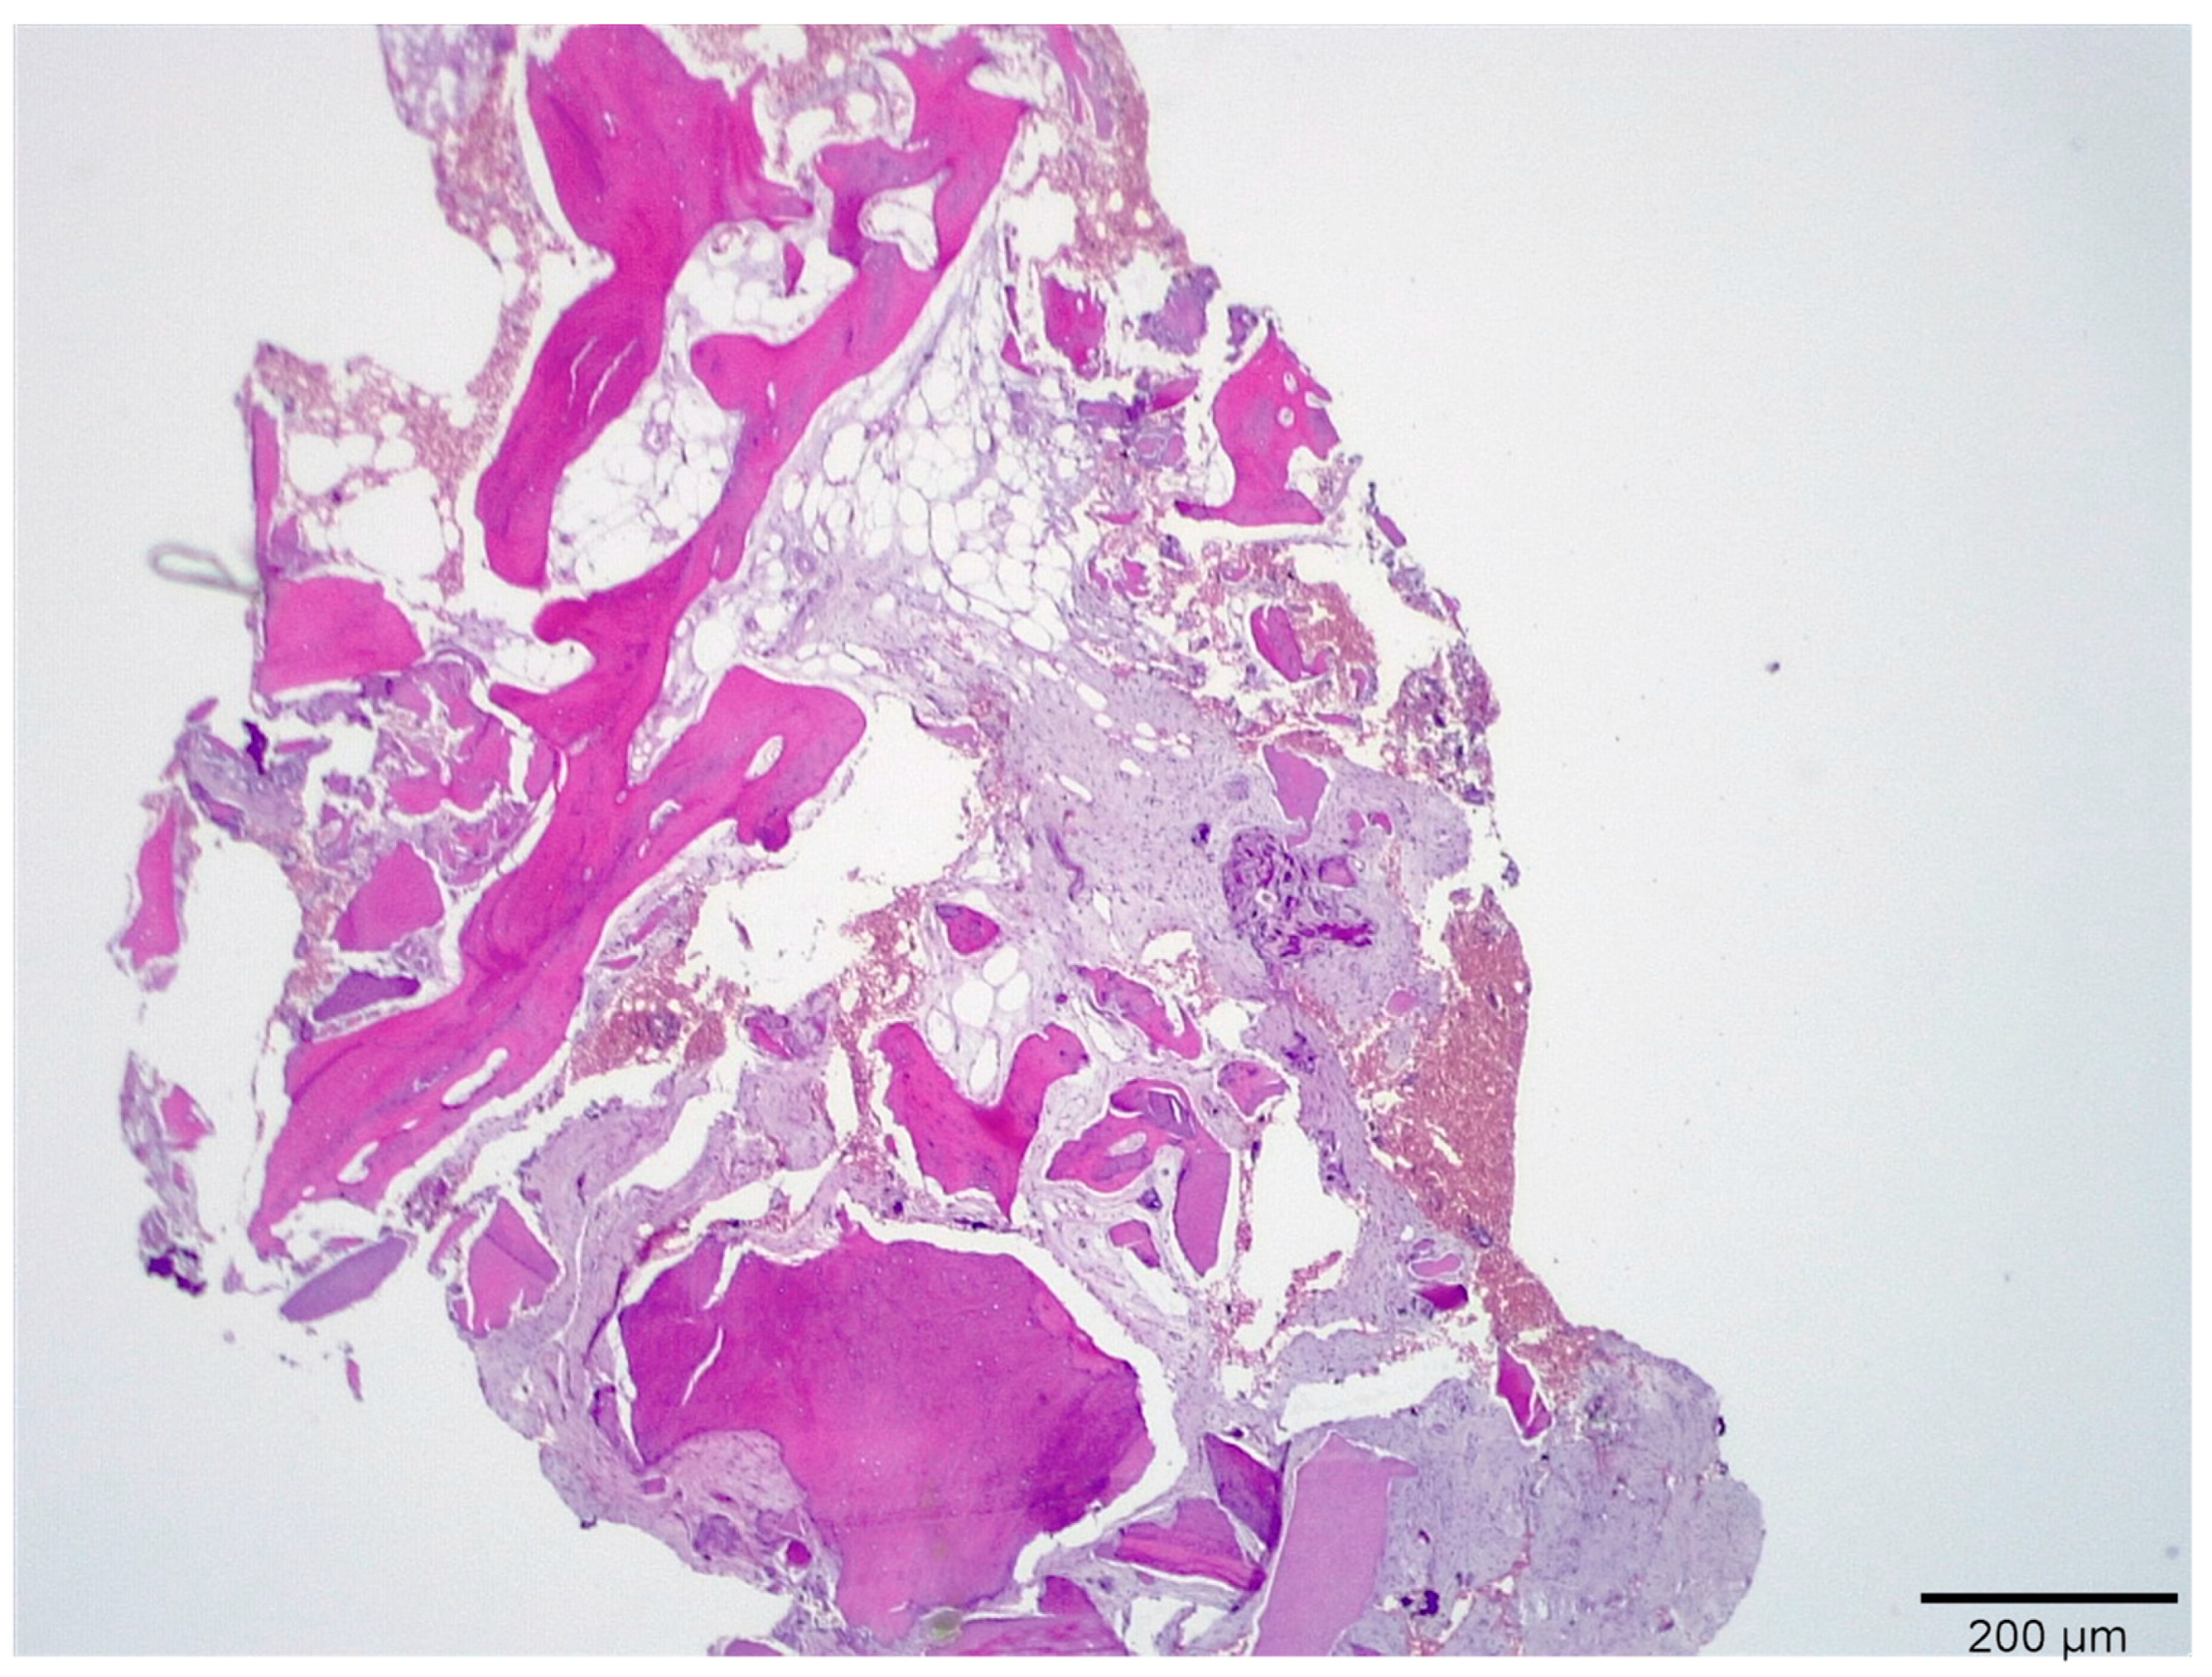

3.1. Histological Analysis Showed Signs of New Bone Formation at 60 Days

3.2. Histologic Data Obtained after Samples Analysis at 24 Months of Evaluation